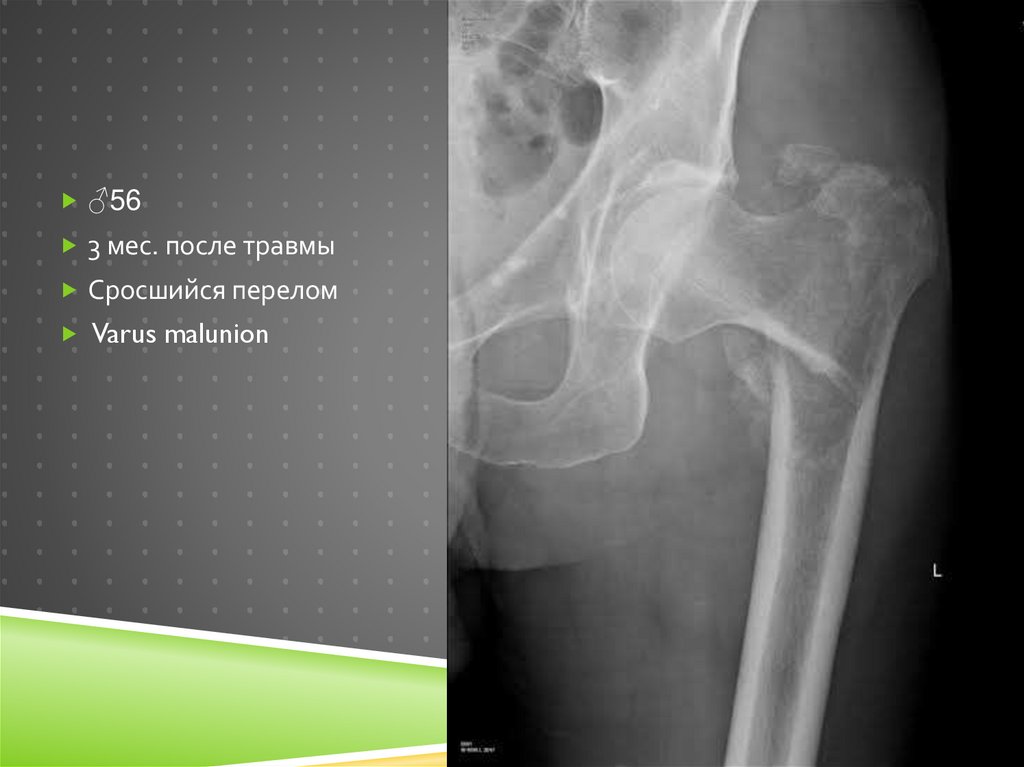

♂56

3 мес. после травмы

Сросшийся перелом

Varus malunion